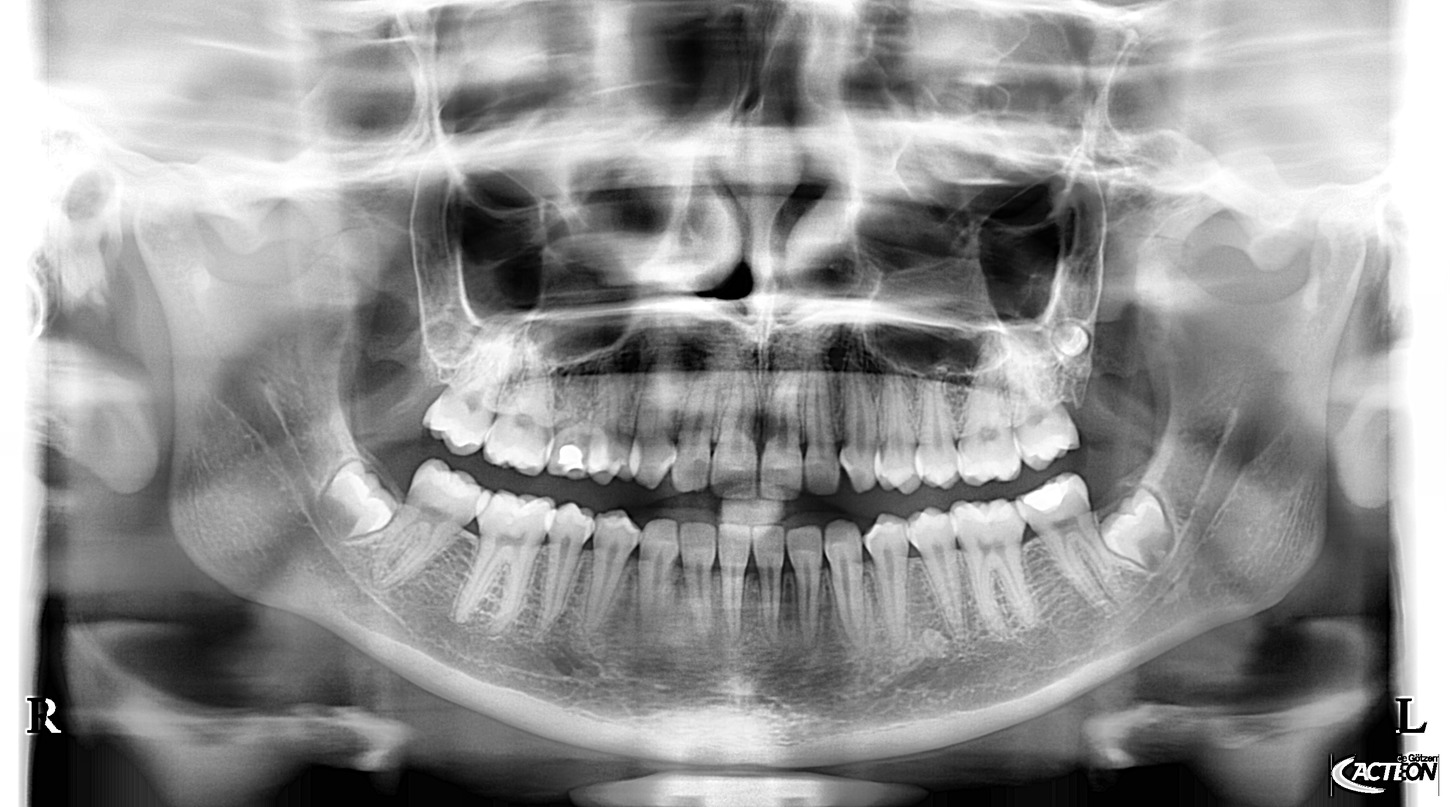

Panoramatické RTG s kefalo projekcí od výrobce Acteon (Satelec), jsou svými parametry a cenovou dostupností nejlepší volbou pro stomatologické praxe. Jedná se o OPG s kefalo ramenem, která svou kvalitou a ovládáním předčí všechna očekávání a řadí se tak mezi nejpoužívanější OPG v ortodontických ordinacích ve světě i u nás. Společnost Fénix Dental dodává všechny přístroje s odborným zaškolením a to dle individuální potřeby každého uživatele. Díky Aies SW je zobrazení OPG snímků bezkonkurenční. Díky panoramatickému RTG od výrobce Acteon, získáte nejpřesnější diagnostickou hodnotu, která snese ta nejpřísnější měřítka. Společnost Fénix Dental je autorizovaný servis pro produkty Acteon. Získejte precizní, přesné a kvalitní OPG snímky, kontaktujte nás.